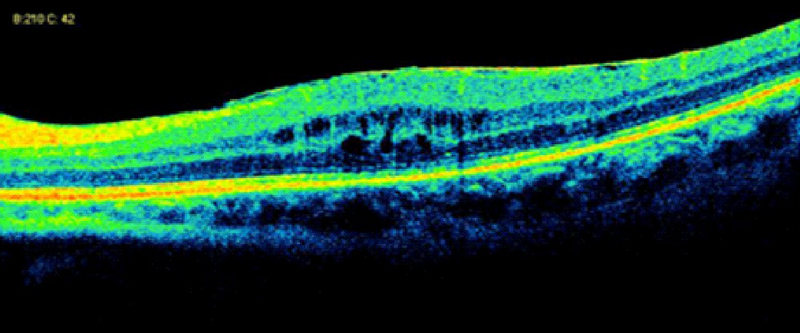

Forooghian

et al16 estudiaron la presencia de atrofia foveal en un grupo heterogéneo de pacientes con uveítis usando imágenes de OCT de alta definición (HD-OCT). Con Cirrus HD-OCT, los autores definieron la atrofia foveal como un punto central de grosor foveal <150 µm. Los diagnósticos más frecuentemente asociados a atrofia foveal fueron uveítis asociada a enfermedad de Behçet, coroidopatía serpiginosa y oftalmía simpática (13%, respectivamente), seguidas de otras uveítis posteriores, intermedias y panuveítis.

La causa de la atrofia foveal es multifactorial e incluye disfunción y atrofia del EPR y la coroides, antecedente de EMQ de larga evolución, isquemia macular secundaria a vasculitis oclusiva retiniana, neovascularización coroidea, desprendimiento de retina y posiblemente daño directo a través de anticuerpos contra los fotorreceptores. Los autores sugieren una observación cuidadosa de las uniones entre los segmentos internos (SI) y externos (SE) de los fotorreceptores mediante HD-OCT para identificar aquellos pacientes con riesgo de pérdida visual secundaria a atrofia foveal.

La integridad de la capa de los fotorreceptores se determina a través del análisis de los SI/SE, que es la llamada capa de los elipsoides. El estado entre la unión de los SI/SE se ha asociado a diferencias significativas en cuanto a la agudeza visual, de forma que la disrupción o incluso la desaparición de la capa de los elipsoides en la OCT se correlaciona con un mal pronóstico visual (

Figura 12 y

Figura 13).